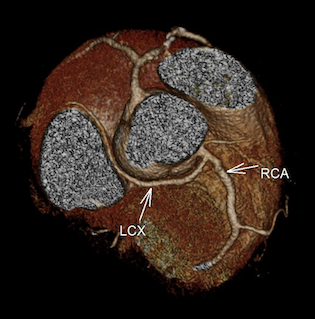

CASE 1- Coronary anomaly- LCX FROM RCA

Anomalous origin of the Left Circumflex artery from Right Coronary artery identified by imaging with Multidetector Computed Tomography

On MDCT angiography, left coronary artery was seen to arise from the left sinus of valsalva which further coursed along the anterior interventricular groove as LAD. RCA was seen to be arising from anterior aortic sinus with its normal course along right atrio-ventricular (AV) groove. There was a vessel seen arising form its proximal segment which took a retro-aortic course towards the left AV groove. It was labelled as LCX as it followed the normal course of the LCX along left AV groove.